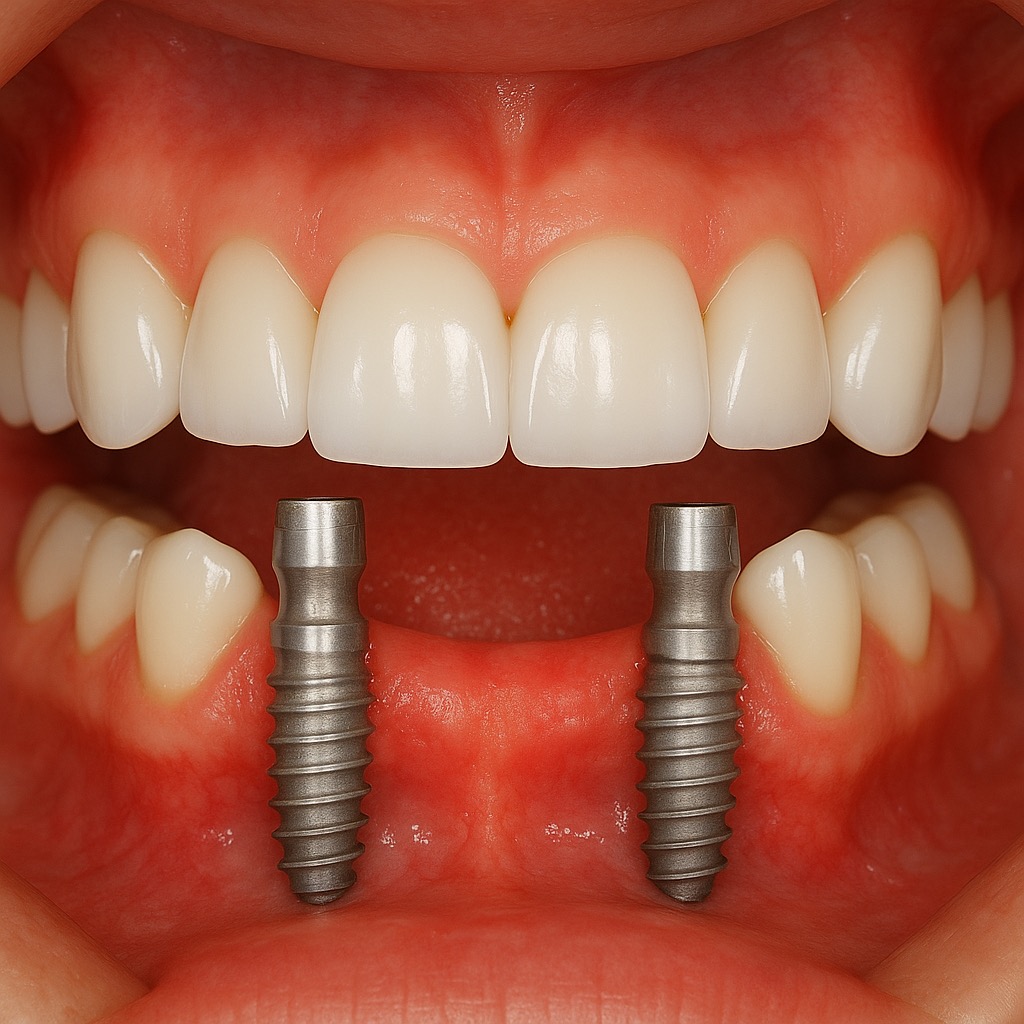

New patients can enjoy a comprehensive exam, panoramic X-ray, and bitewings, plus a complimentary consultation for Botox, dental implants, or a digital scan for Invisalign.